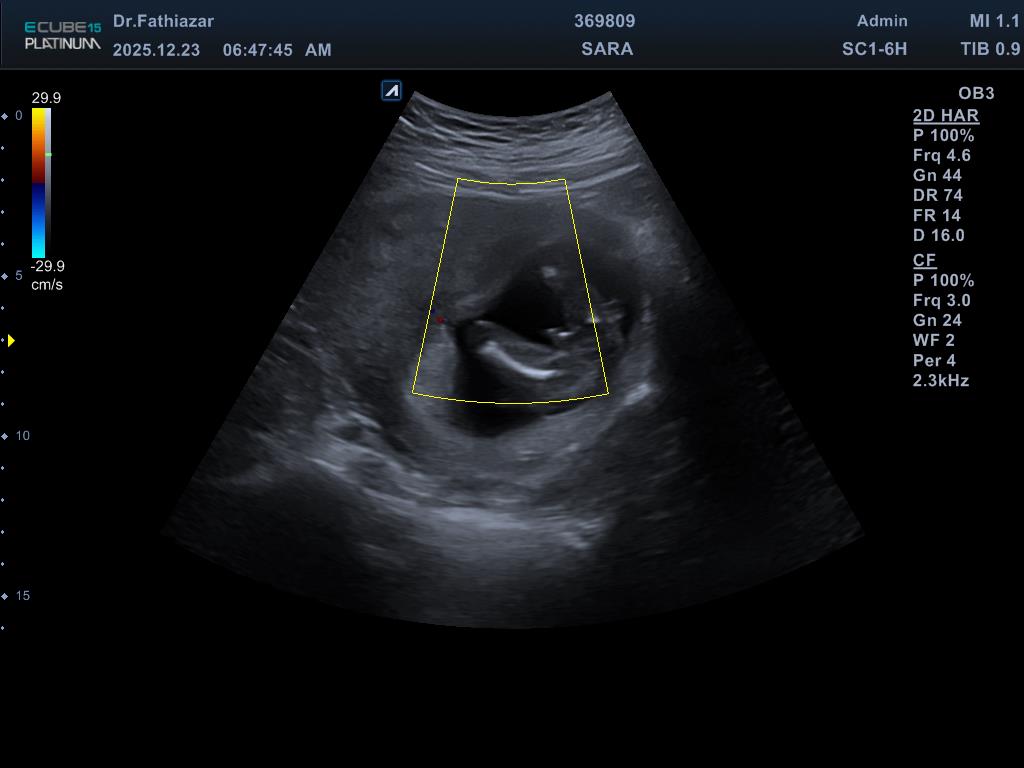

سلام به نظرتون جنسیت بچه پسر یا دختر چون میگن امکان داره اونی وسط پاهاشه میتونه دست یا ناقض باشه دکتر بهم گفته پنجاه درصد احتمال پسره